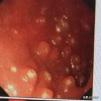

その通り、ポリープは多くの人が思い浮かべるポリープとほとんど同じで、平たく言えば、腸にできる肉のようなコブのようなものだ!ポリープは体の消化管全体にできる可能性があり、結腸ポリープと直腸ポリープが最も一般的で、小腸ポリープはそれほど一般的ではありません。

一般に、病理学的性質がはっきりしないものは大腸ポリープと呼ばれる。

もちろん、ポリープは腫瘍性と非腫瘍性に分けられる!

一般的に、炎症性ポリープ、過形成性ポリープ、不整形ポリープなどは非腫瘍性ポリープです;

一方、腺腫性ポリープは、癌になる可能性があるため、腫瘍性のポリープである!

しかし、非腫瘍性のポリープであっても、大きくなりすぎると癌化する可能性がある!